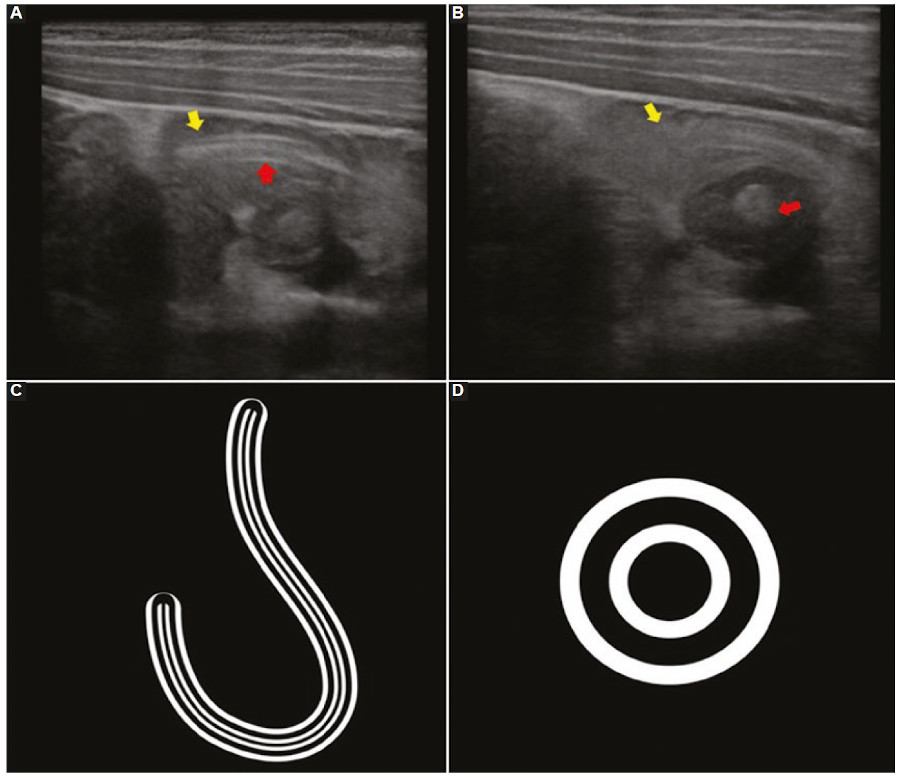

- Caso 2. Se trata de un niño de cinco años de edad cursando internación por neumonía en su tercer día de tratamiento antibiótico, intercurre con dolor en hipocondrio derecho asociado a náuseas y vómitos de cuatro horas de evolución. Ante estos síntomas inespecíficos se le solicita una ecografía abdominal (Fig. 2).

En la ecografía se identifican signos particulares como el de la “masa de gusanos” y del “doble tubo”. Este último hace referencia a la visualización intestinal intraluminal de dos líneas ecogénicas externas y otras dos internas de similares características con un área central hipoecogénica que representa el tracto gastrointestinal del parásito (Figs. 1A y 2 A y C); esta misma imagen vista en corte transversal conforma el “signo del ojo de buey” (Fig. 2 B y D). Se menciona como hallazgo adicional frecuente y de ayuda diagnóstica el desplazamiento del parásito mediante movimientos peristálticos y de ondulación durante la realización del estudio.